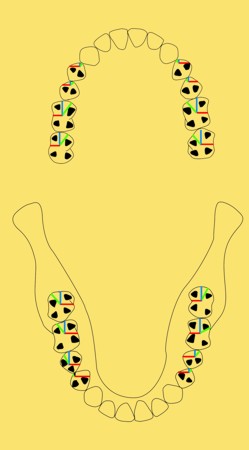

Primera Parte RESUMEN: La alta complejidad inherente a los procedimientos de Rehabilitación Oral, obligan al profesional que la ejerce a basarse en parámetros multidisciplinarios, a veces lo suficientemente intrincados que hacen imposible la práctica de la misma, sin la presencia en su mente de una clara concepción de la Oclusión. The extreme complexity of Oral Procedures, make it imperative for the working professional to rest on multidisciplinary parameters, sometimes so complex that make impossible its practice without the presence of a clear idea of Oclusion. DESARROLLO Suele ser sumamente árido el abordaje de un tema como Oclusión, desde la perspectiva de nuestro diario trabajo ,con todo el strees que este conlleva, con toda la lucha que significan citas, honorarios, diferentes personalidades de los pacientes, inquietudes de los mismos, etc. «LA MEJOR OCLUSIÓN ES LA QUE TIENE LA MEJOR DESOCLUSIÓN» Básicamente, podemos como desde hace ya muchos años se viene haciendo; clasificarlos en: A)Determinantes Posteriores (fijos) Más contemporáneamente, en: I-Mecanismos Primarios: A.T.M. GUIA ANTERIOR INCLINACIÓN DEL PLANO OCLUSAL CURVA SAGITAL DE SPEE FORMA DE LA ARCADA III-Mecanismos Elementales CRESTAS TRIANGULARES INTERNAS Analicemos cada uno de ellos: Es evidente, que la reproducción de las características de la A.T.M., en nuestro aliado fundamental, el Articulador; es imprescindible. Partiendo de la premisa de obtener una OCLUSIÓN MUTUAMENTE PROTEGIDA, para luego arribar al concepto de OCLUSIÓN MUTUAMENTE COMPARTIDA, concepto este que desarrollaremos durante el transcurso de las distintas entregas, analizaremos cada uno de los FACTORES DETERMINANTES DE LA OCLUSIÓN. El primero de ellos, por ser fijo e invariable, solo diremos que: son sus INCLINACIONES PLANARES, o sea : A-INCLINACIÓN DE LA TRAYECTORIA CONDILEA C-BENNET INMEDIATO articuladores totalmente ajustables) D-DISTANCIA INTERCONDILAR. En cuanto a la GUÍA ANTERIOR, mecanismo primario y por supuesto anterior, provee al cuerpo mandibular; del camino a recorrer durante las excursiones protrusivas y lateralidades, a través del vínculo entre las piezas dentarias anteriores, superiores e inferiores. En un corte sagital, podemos observar la relación entre estos donde vemos que se vinculan sin entrar en un contacto franco, sino más bien en una relación de vencindad muy intima a la que llamamos: PUNTO DE ACOPLAMIENTO. Otros factores fundamentales de la GUÍA ANTERIOR son : A-ALTURA FUNCIONAL B-PUNTO DE ACOPLAMIENTO En cuanto a los SURCOS, sabemos que durante una Transtrusión, las cúspides fundamentales generan surcos sobre las piezas que antagonizan. Dichos surcos proveen de una vía de escape a las cúspides antagonistas para evitar colisiones, con las indeseables fuerzas laterales cuya gravedad ya conocemos. MECANISMOS SECUNDARIOS La CURVA FRONTAL DE WILSON, se observa invertida a nivel de los caninos y de los primeros premolares. El PLANO OCLUSAL, en realidad no es ningún plano, sino la sumatoria de muchos MICROPLANOS, los cuales individualmente pueden constituir factores presentes en la OCLUSIÓN, pero auténticos problemas para la DISCLUSIÓN. La CURVA SAGITAL DE SPEE, denominada originariamente de BALKWIL-SPEE, fue concebida como una curva. El cuarto factor SECUNDARIO: el ANCHO DE LA ARCADA, es evidente que variando los ejes de rotación , alrededor de las diferentes distancias ;cambiará la dirección de los escapes (surcos), de los elementos que en el se muevan (cúspides). MECANISMOS ELEMENTALES Los CUATRO NIVELES DE OCLUSIÓN y las CRESTAS TRIANGULARES INTERNAS, constituyen de por si, la herramienta ejecutora de las funciones gnáticas. A- ELEVACIONES 1-Puntas Cuspídeas B-DEPRESIONES 1-Fosas SURCOS DE DESARROLLO De las CRESTAS TRIANGULARES INTERNAS, acentuamos su importancia en ellas dado que son las efectoras finales de la molienda, y su triangularidad debe tener su base partiendo del surco y su vértice terminando en la Punta Cuspídea, condición importante para evitar colisiones durante la transtrusión (movimiento de lateralidad ). EFECTOS DE LA VARIABILIDAD DE LOS FACTORES DETERMINANTES DE LA OCLUSÍON Cada uno de los determinantes influye aumentando o disminuyendo tanto la DESOCLUSIÓN como la ALTURA CUSPÍDEA INCLINACIÓN DE LA TRAYECTORIA SAGITAL INCLINACIÓN DEL PLANO OCLUSAL RADIO DE CURVATURA DE LA ÁNGULO DE LA TRAYECTORIA ALTURA DEL PUNTO DE LATERO SURTRUSIÓN / MOV. DE BENNET INMEDIATO CURVA FRONTAL DE WILSON SURCOS BIBLIOGRAFÍA Dibujos y esquemas tomados del libro: Oclusión Orgánica…un camino hacia la Rehabilitación Oral. 1)William Mc Horris,B.S.,D.D.S. Oclusión. Con especial énfasis sobre :El rol funcional y parafuncional de los dientes anteriores. 2)Von Spee , Craff(Anatomista alemán, describió la curva de compensación de la articulación de molares y premolares).CURVA DE SPEE 1.89 3)Stuart,D.»Some aspects of the inervation teeth.»Procedings of Royal Society of Medicine.20:1675,19274)Muhleman,H. y Savdir,S»Tooth movility-its causes and significance»Journal of Periodontology ,36:153,Marzo ,Abril,1965. 4)Muhleman,H. Y Savdir,S»Toothmovility its causes and significance» Journal of Periodontology,36:153,marzo,abril,1965. 5-Oclusión y Diagnóstico en Rehabilitación Oral. 6-Anatomia Odontológica. -A contribution to the study of the movementes of the mandible. 8-Celenza F.W, Nadeskin J.F.,Oclusión.Situación actual. 9-D´Amico 10-Dawson P.E. 11-Huffman -Regenos. 12-Hobo S.-Takayama H.A. 13-Lucia V.O 14-Mc Horris. 15-Mc Horris. 13-Posselt U. 16-Stuart C. 17-Vartan Veshnilian

CUATRO NIVELES DE LA OCLUSIÓN

De los primeros diremos que podemos dividirlos en:

2-Rebordes(Marginales y Transversos)

2-Surcos (de Desarrollo y Suplementarios)

CRESTAS CENTRALES REBORD.MARGINALES